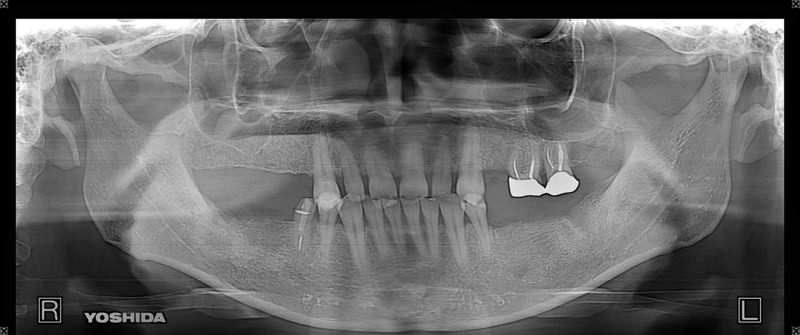

症例140代 男性 主訴 奥歯に歯を入れたい、しっかり噛みたい

治療前

治療後(5年経過)

※説明

主訴 奥歯がない為、食事が不自由である。入れ歯は煩わしいので、固定制のインプラントにして欲しいと訴え来院。口腔内全体で6本のインプラントを埋入。仮歯にて神経筋機構、顎関節のバランスを整え、リハビリを経て、約5ヶ月後にジルコニアを装着。

リスクとしては、外科的侵襲がある。デメリットは、保険外診療の為、経済的負担がある。

費用 316万(税込) (オペ・仮歯・最終補綴物まで含む)